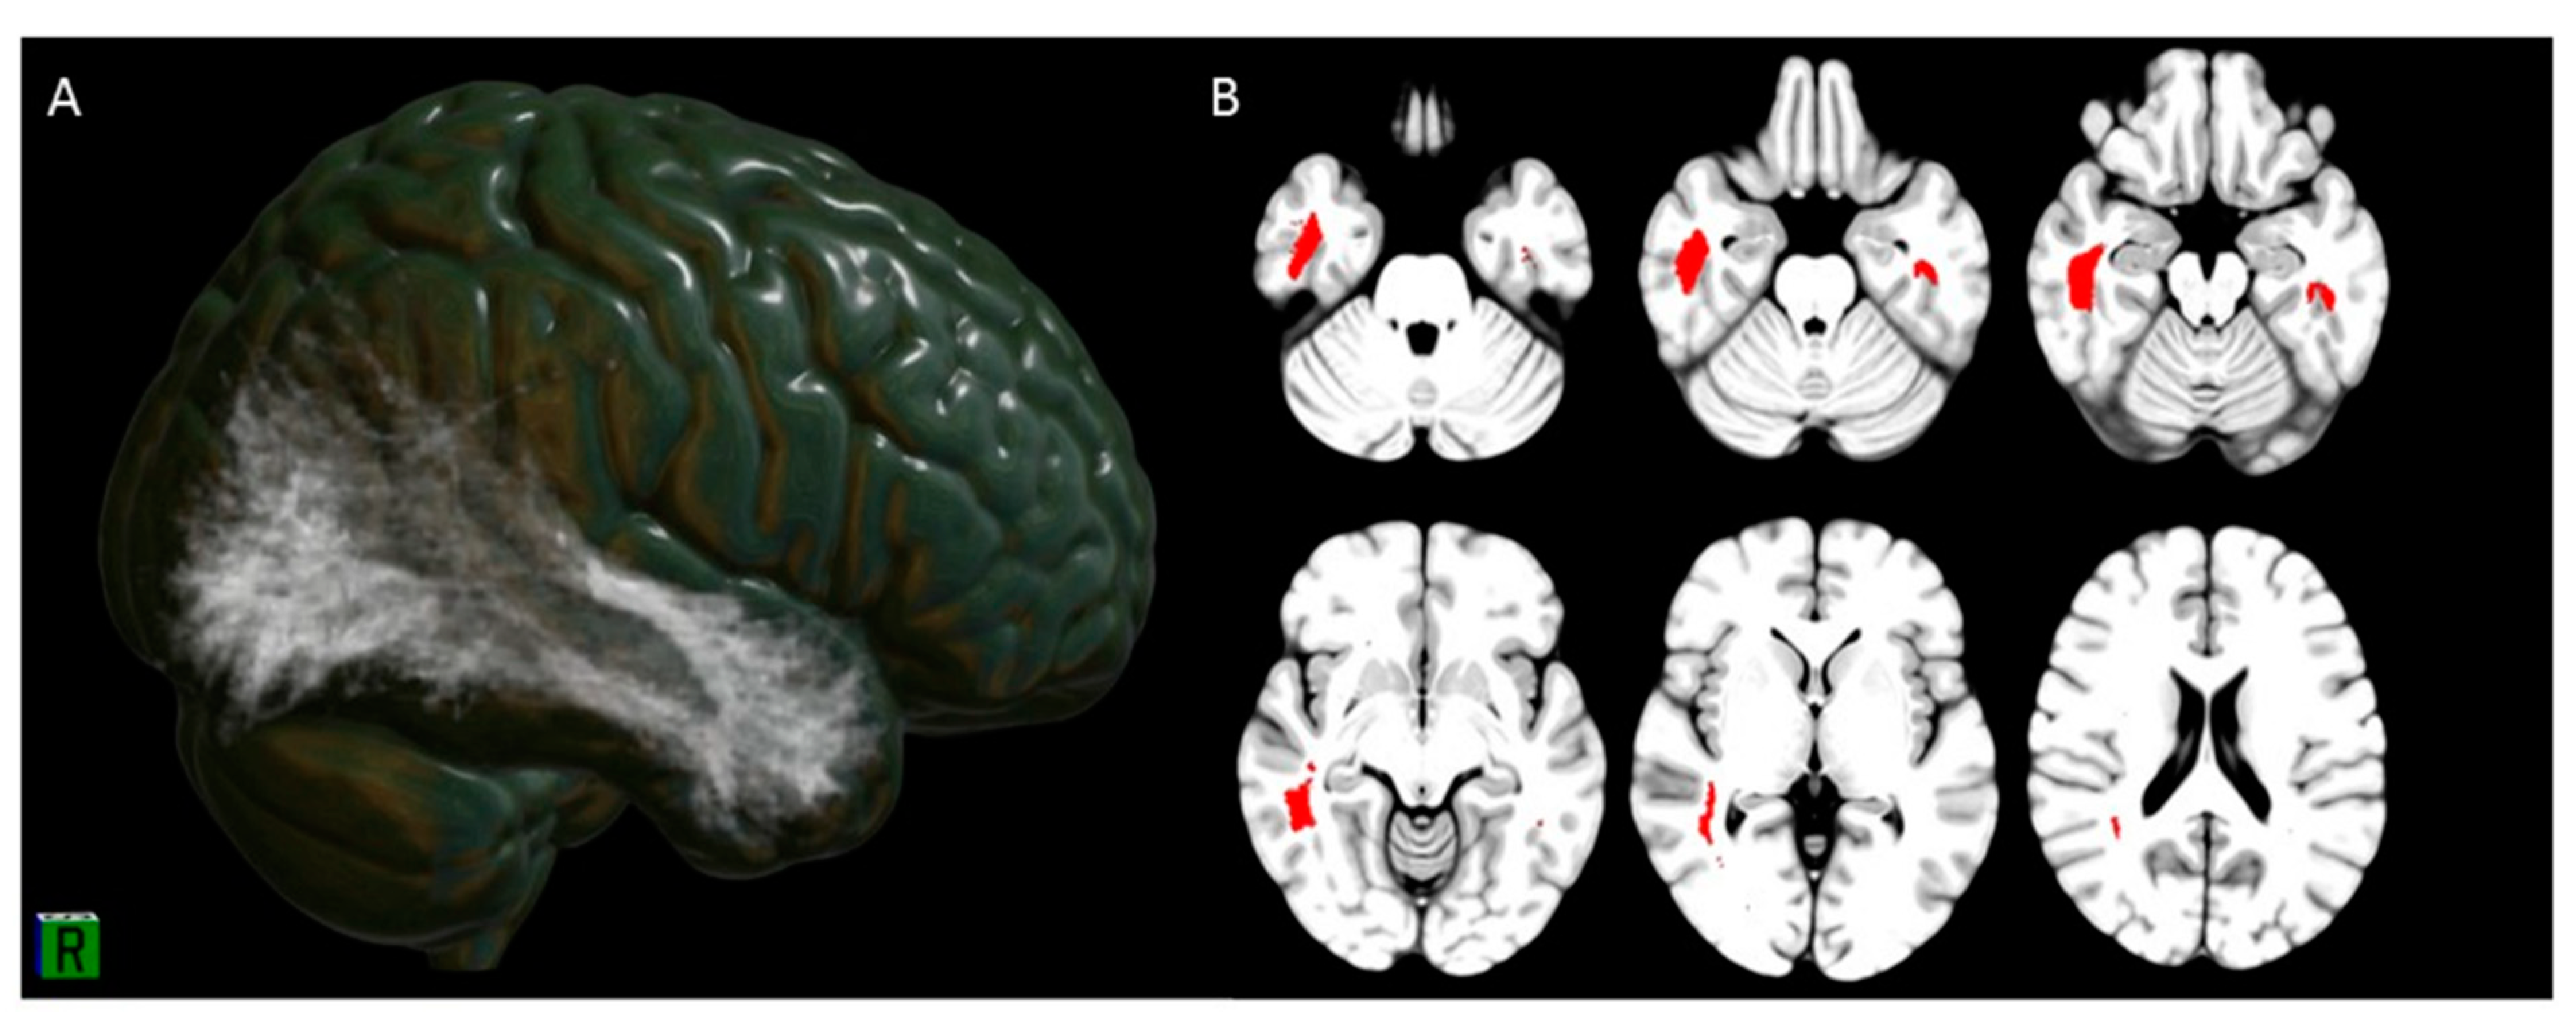

3.3. Hyposmia Clusters Tractography and Connectivity